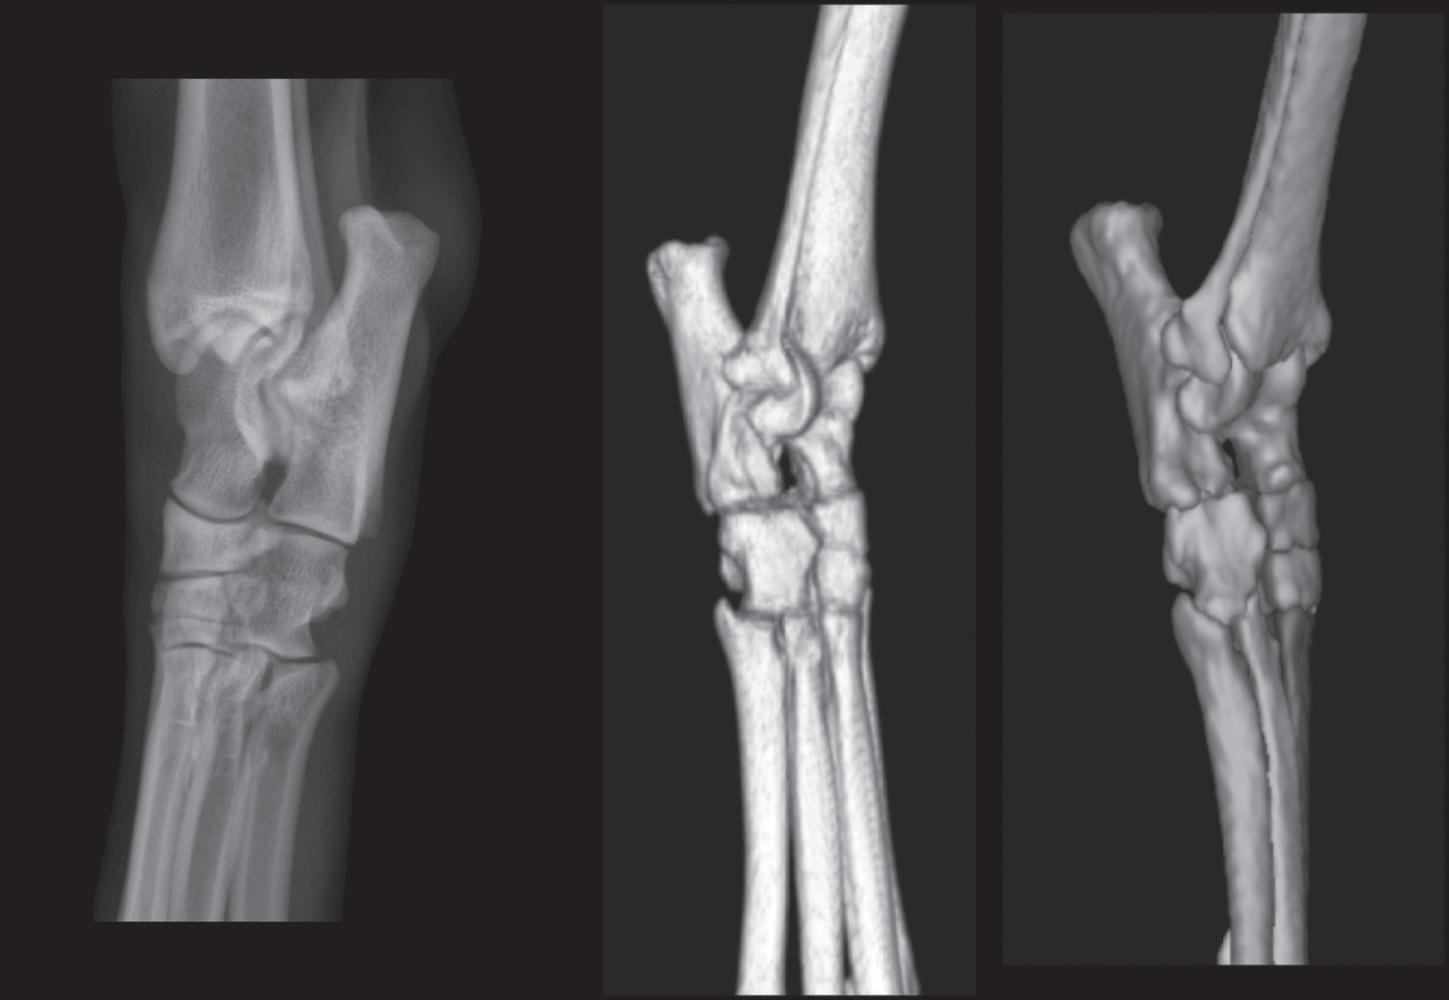

A radiograph is a 2-dimensional image of a 3-dimensional (3D) object. As a result, structures cannot always be accurately localized spatially in radiographs, even with multiple views. CT images are tomographic, creating multiple image slices of the patient. Slicing the patient solves the problem of spatial localization and can assist with understanding radiographic anatomy more thoroughly. Additionally, transverse plane CT images can be reformatted into sagittal and/or dorsal plane images for clarifcation or to improve structure visualization. Transverse CT images can even be reformatted into 3D volumetric images for depicting more complex structures. Therefore, a selection of CT images has been included.

The best solution for accurate imaging of a complex structure is to use a tomographic imaging modality. As noted earlier, tomographic imaging modalities display images in slices, thus completely avoiding the problem of superimposition. Ultrasound, CT, and MR images are all tomographic. If tomographic imaging is not possible, the use of oblique radiographic projections can also reduce the complexity created by the superimposition of structures.